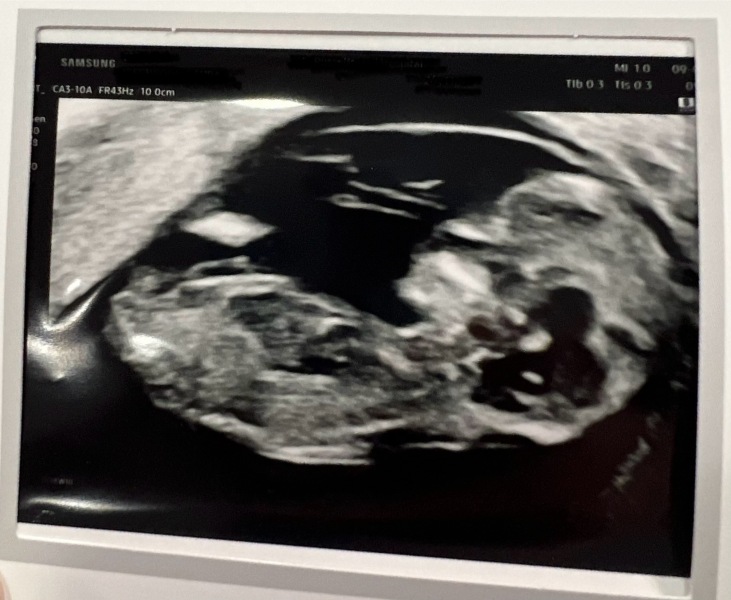

Just wanted to share that I had a very successful 12 week scan! Brought my due date forward by a couple of days to 20th March 🌸 baby did not like being prodded with the ultrasound probe and performed many forward rolls and flips - may have the next Team GB gymnastics gold medalist! But we got a little thumbs up, a picture of their foot and them also doing the downward dog pose! The sonographer did say it was a feisty baby 😂

I know you can’t see the nub but I’m just getting boy vibes!

Congrats @DogMom62...what a lovely scan picture 😍.